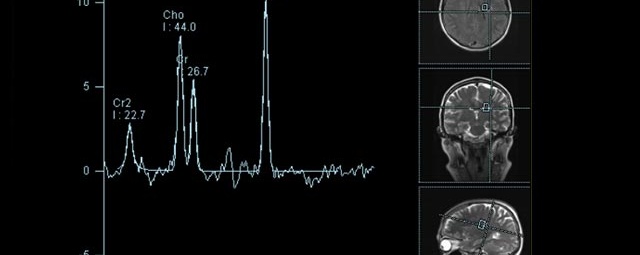

- Diffusionswichtung

- Perfusionswichtung

- Suszeptibilitätswichtung

- MR-Spektroskopie

Diese Verfahren werden bei verschiedenen Fragestellungen in verschiedenen Körperregionen in die Messprotokolle sinnvoll eingefügt. Teilweise können dadurch Differenzierungenverschiedener krankhafter Prozesse verbessert werden.